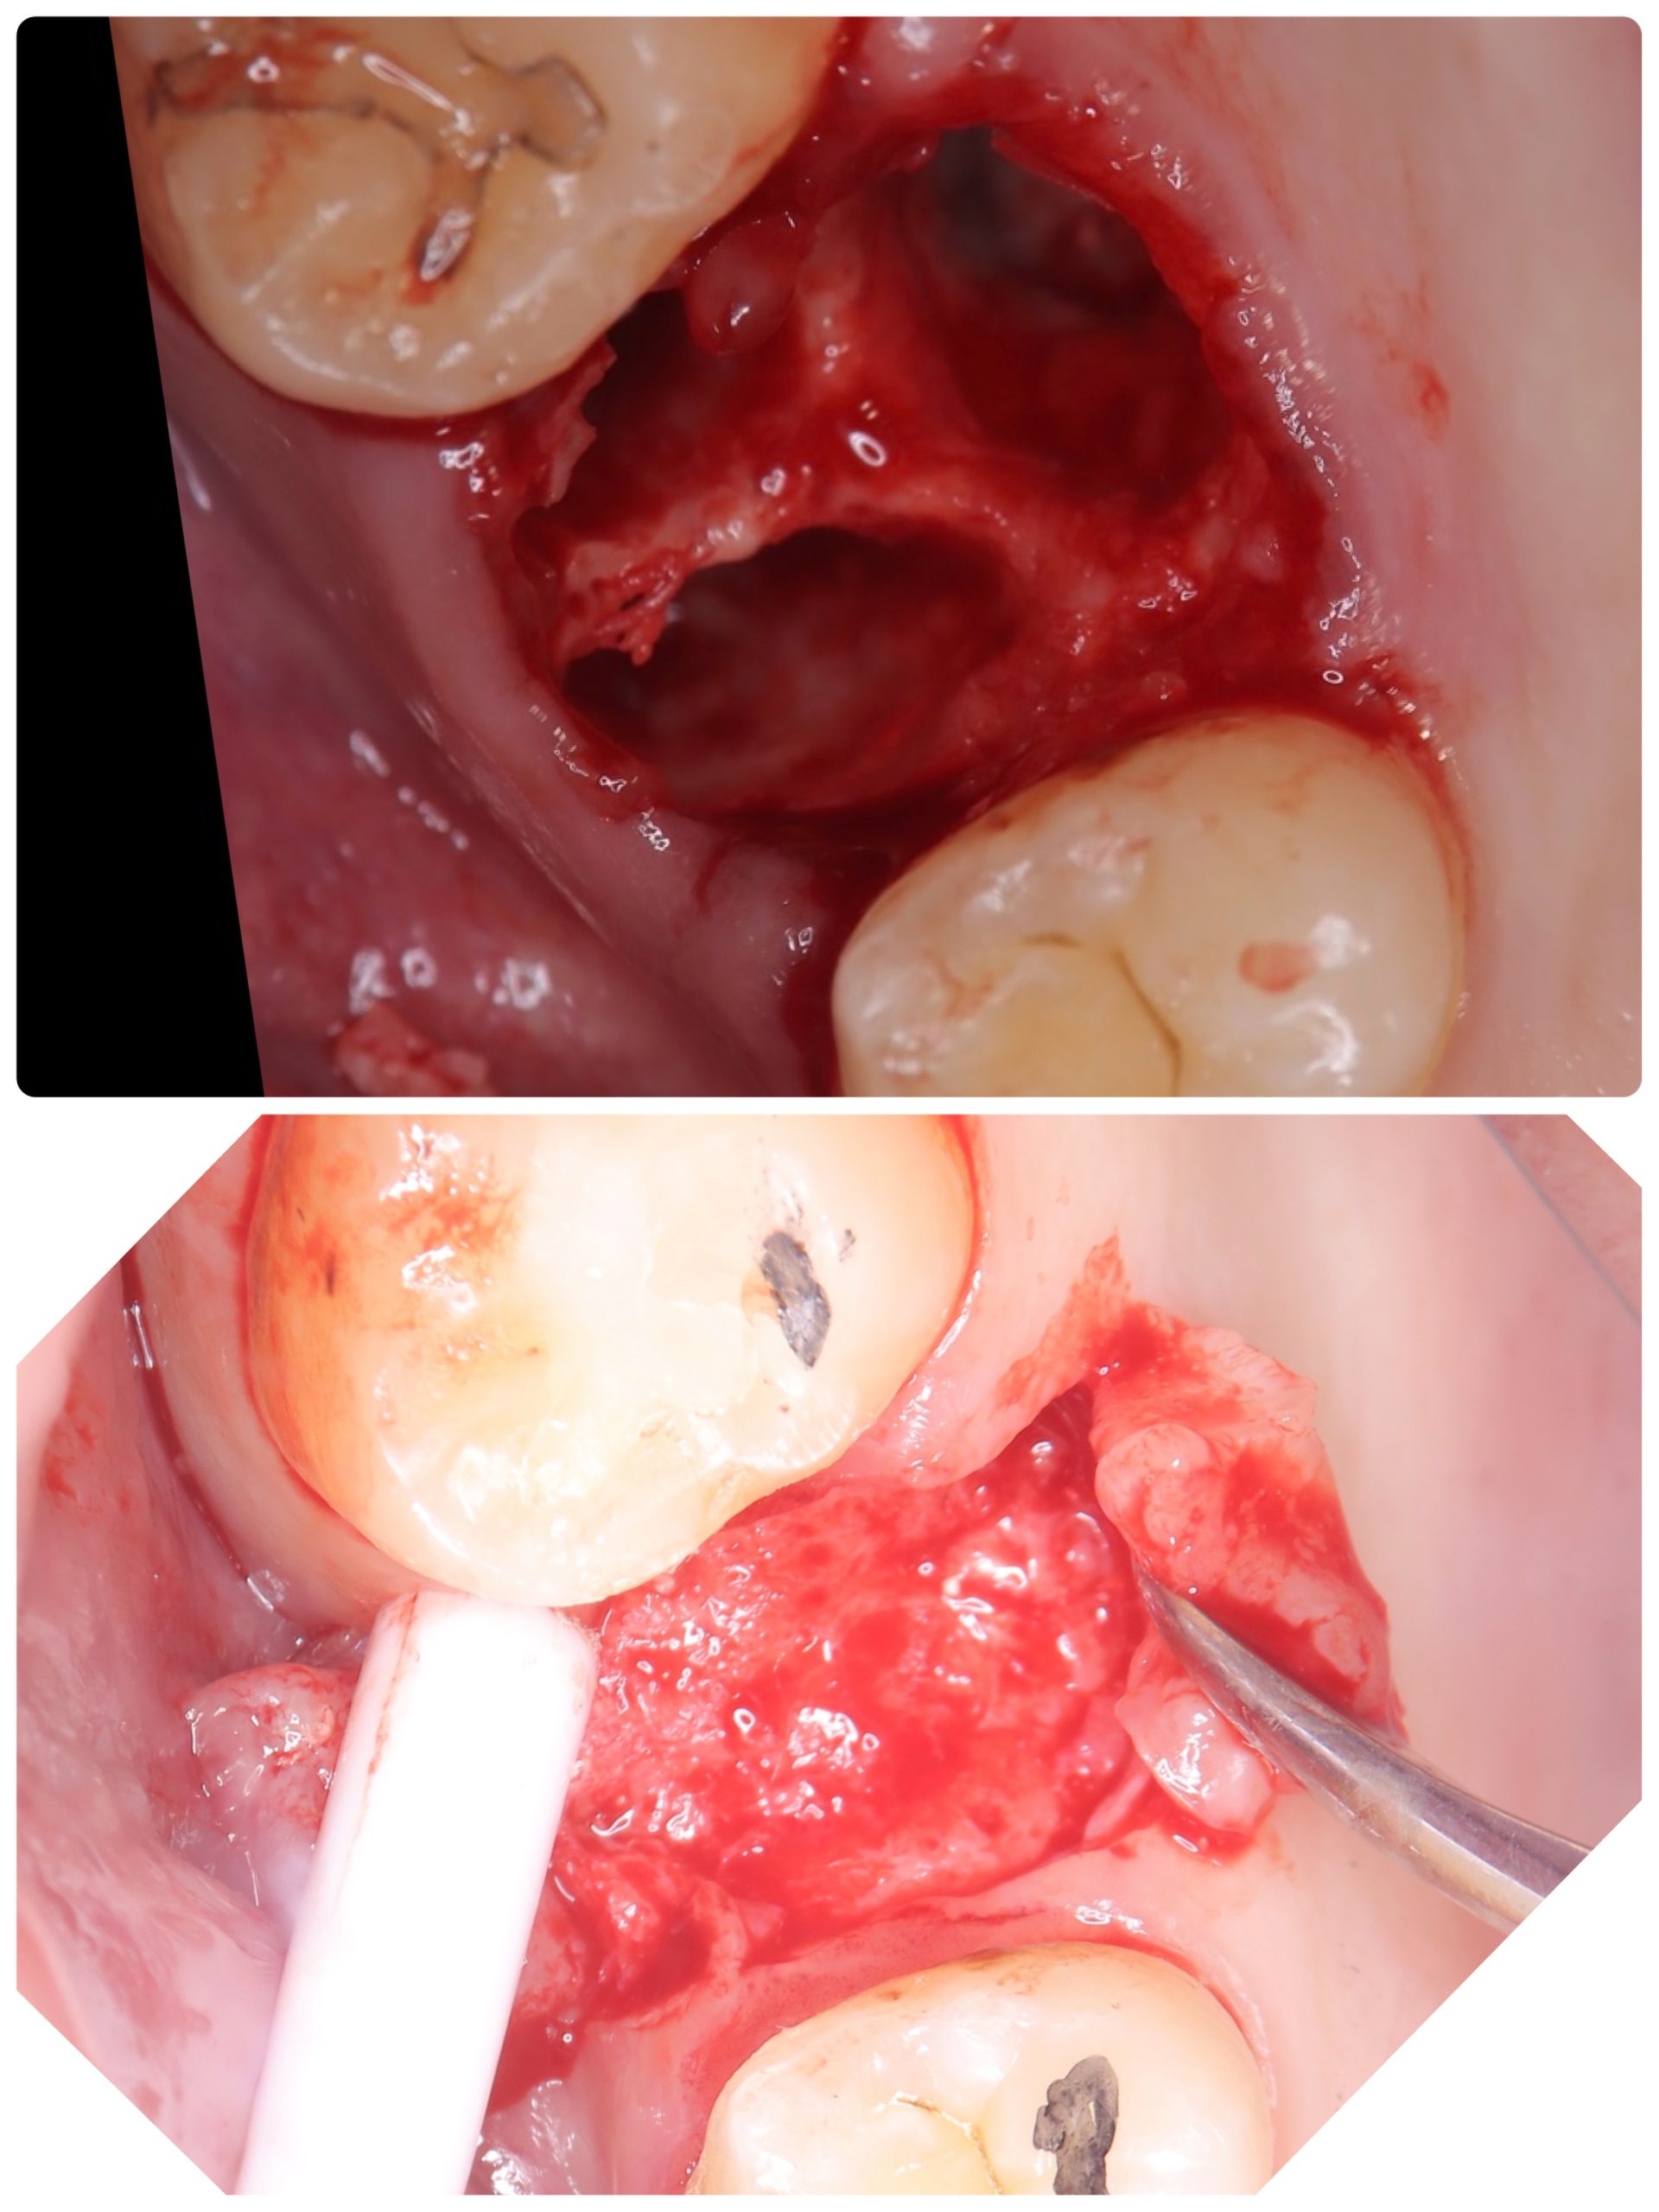

昼間からは、危ない動脈近接のソケットリフト

バッチリ👍避けるコツがある💪

抜歯後2ヶ月待ちオペ、EMDとボナークのお陰です

違いが、分かるかなあ?

5ミリで骨折、自己採血2本メンブレン挿入